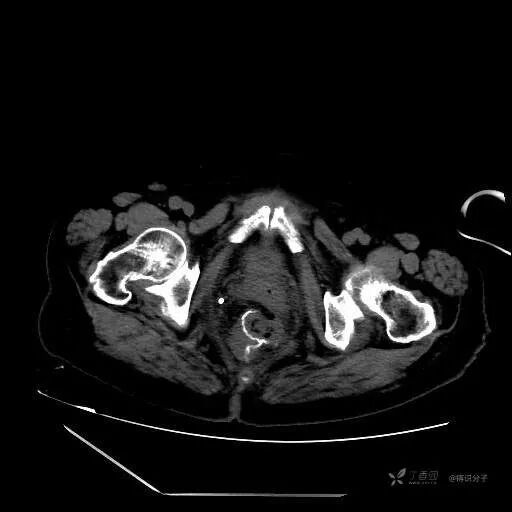

辅助检查:查腹部 CT 示骶前包裹性积液,距离引流管较远,吻合口周围未见明显渗出和气体征象。